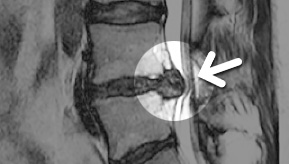

MRI ġ

MRI

ϰ ڻ ͼ ̶ ؿ.

ü Ƶ ̰ ȣ µ

㸮 , ٸ ʹ

, Ƹ, ߰ ļ

ũ Ŀ